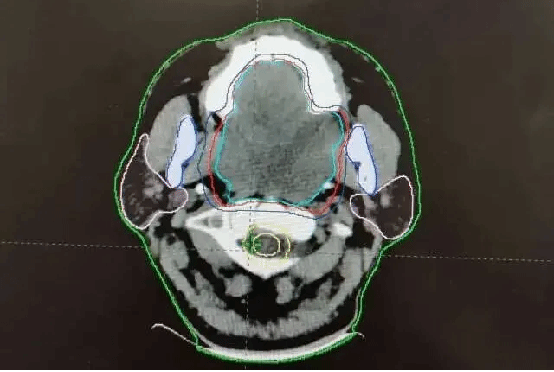

渴望收获安稳睡眠的路先生辗转来到我院放疗科就诊。科室团队迅速启动多学科会诊,针对肿瘤体积大、位置特殊、紧邻重要器官的复杂情况,制定了个体化精准放疗方案。借助先进的影像及放疗技术,团队精准勾勒肿瘤靶区,将高剂量射线精准聚焦于病灶,在最大限度保护周围正常组织的同时,对肿瘤展开集中“攻坚”。

放疗过程中,医护团队全程密切监测路先生的身体反应,及时调整治疗细节,给予专业的护理指导与心理支持。随着放疗周期推进,奇迹逐渐显现:肿瘤开始逐步缩小,气道压迫症状明显缓解,路先生的呼吸越来越顺畅。治疗结束后复查显示,肿瘤体积较治疗前显著缩小,气道通畅度恢复正常——他终于能平躺在床上,安然进入久违的深度睡眠。

治疗后